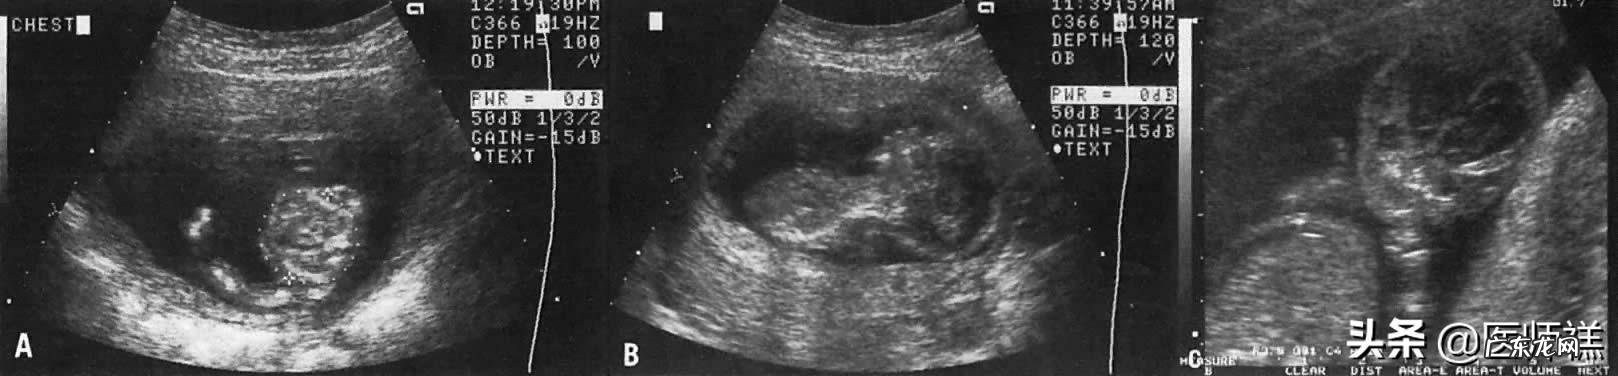

正常生理改变胎儿正常发育:胎儿头部略微超过标准限值很可能是正常的发育改变 。孕妇的身体状态、在孕期摄入的营养状况均会使得胎儿的发育存在一些差异性的改变,营养状态供应足、母亲机体健康状况好有些胎儿的发育要确实要比营养供应不足的胎儿过快一些,如果在其他指标检测都正常的情况下这种现象其实不属于任何病症 。巨大胎儿:相反如果患儿营养供应过足在孕晚期胎儿的体重远远超过正常的4000g,这种营养过剩引起的胎儿发育状态我们也成为巨大胎儿 。巨大胎儿的发生通常是营养过度堆积引起,例如孕妇营养热量摄入过度引起机体过度的肥胖;妊娠过程中孕妇合并糖尿病,胎儿会吸收更多的能量导致体重异常发育过旺;除此以外对于高龄产妇、以及有巨大胎儿分娩史的产妇这种胎儿头大的现象也经常发生 。这种胎儿头大是属于胎儿正常发育范畴并不属于病理性的改变 。但是巨大胎儿常常会容易导致难产,特别是肩部难产很容易导致胎儿窒息死亡 。病理性胎儿头大胎儿脑积水:胎儿脑积水是由于胎儿脑脊液循环异常引发的一种疾病,引起疾病的因素有很多无论是先天性因素还是后天因素都会引起脑积水的发生 。例如下图A.注意手臂,前臂和手腕的长度明显减少 。

B.相对于胸部大小,胎儿头很大 。

C.仔细观察胎儿头部,发现脑积水和一个三叶头骨 。